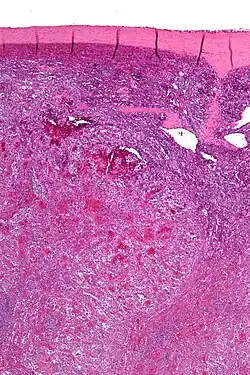

In der Bildgebung sind zahlreiche kleine Knoten in der Milz zu sehen[9]. Im Blutbild kann es zu einer Verringerung von Thrombozyten und Erythrozyten kommen, diese ist allerdings nur bei einem Teil der Patienten zu sehen und nicht beweisend für die Erkrankung. Die Diagnose kann meist erst endgültig bestätigt werden, nachdem die Milz entfernt wurde (Splenektomie). Mikroskopisch beweisend ist eine irreguläre Proliferation Blut gefüllter Kanäle deren Auskleidung negativ für CD34 sind. Weitere morphologische und immunhistochemische Eigenschaften (CD68, CD31) können die Diagnose weiter sichern[10].